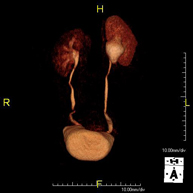

- RM Riñones

Prueba diagnóstica no invasiva que consiste en la obtención de imágenes de alta definición anatómica de ambos riñones mediante el empleo de un campo electromagnético y ondas de radio (con un emisor y un receptor). No utiliza radiación ionizante. Se realiza para estudiar cualquier lesión localizada en ambos riñones. Normalmente se requiere el uso de contraste paramagnético (Gadolinio) para caracterizar las lesiones.